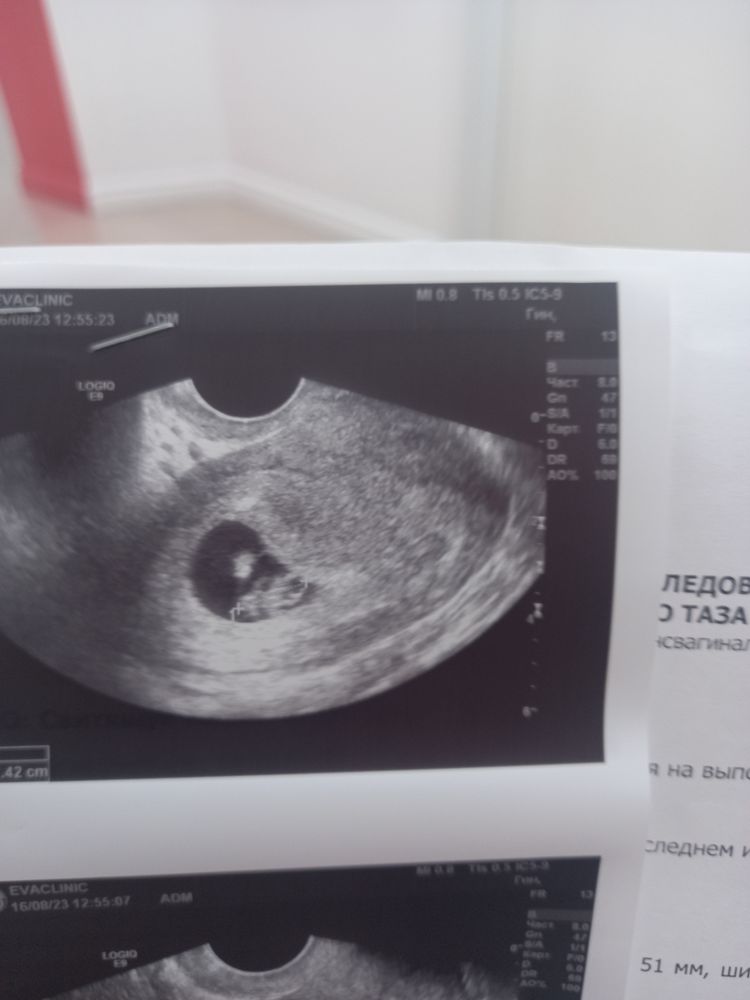

Как хорошо, что я их не послушала. Сейчас 7,5 акушерских недель, и вот такое чудо у меня внутри🥰🥰🥰